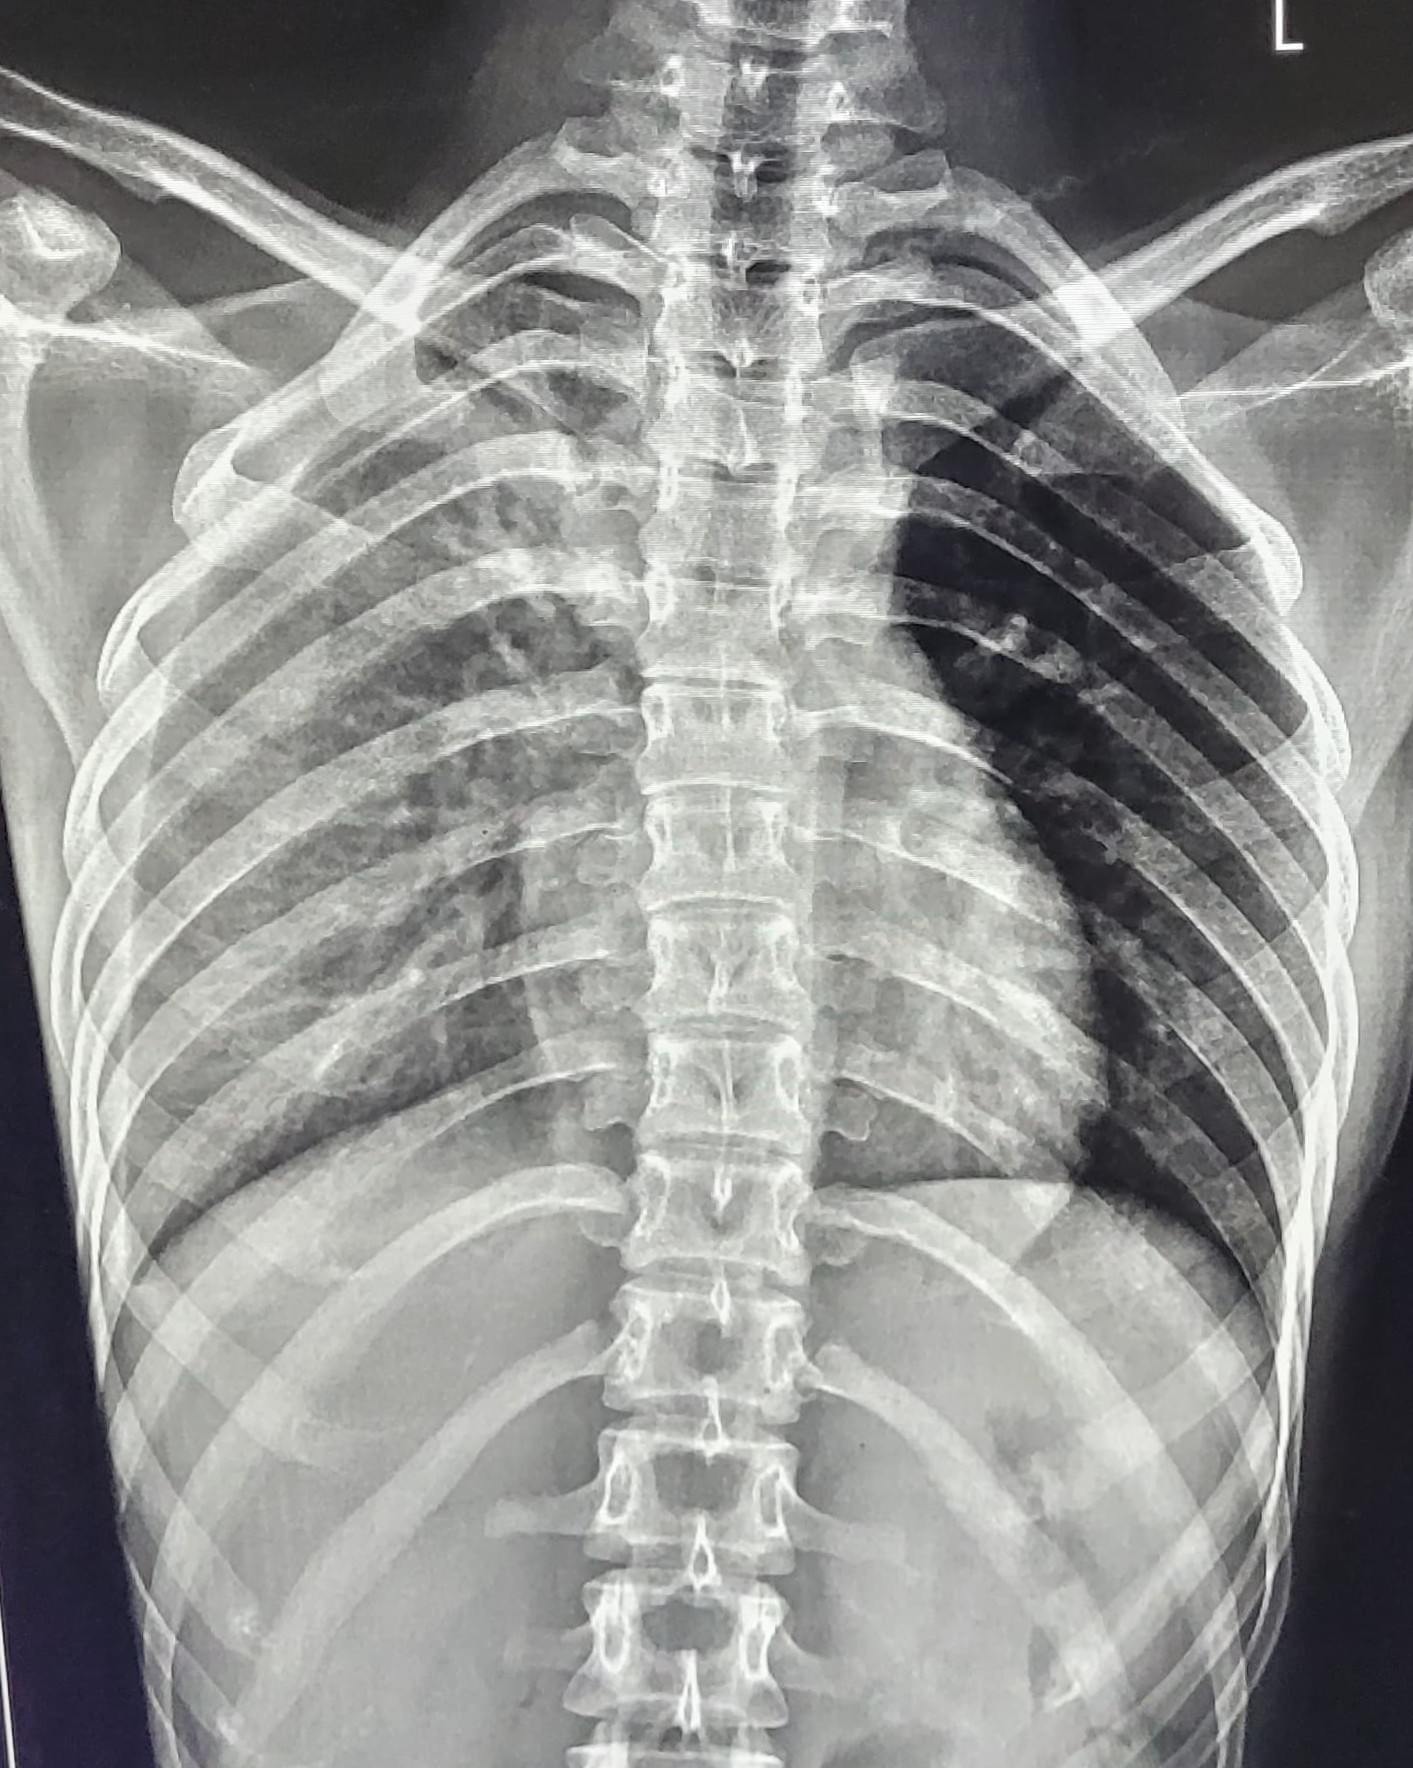

| 201 | IGGMC, Nagpur, Nagpur | P2 | 29-4271 | BUSHRA KHAN | Consent taken on Paper | 21 Yrs. |

Provisional Diag : PTB?

Final Diag : RIGHT SIDED CLINICALLY DIAGNOSED TUBERCULAR PLEURAL EFFUSION |

TB Case (Confirmed) | RIGHT SIDED PLEURAL EFFUSION | Abnormality visible on x-ray |